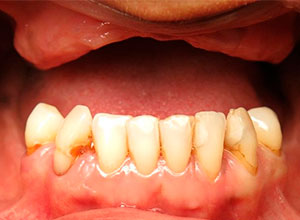

Después con Prótesis Definitiva fija